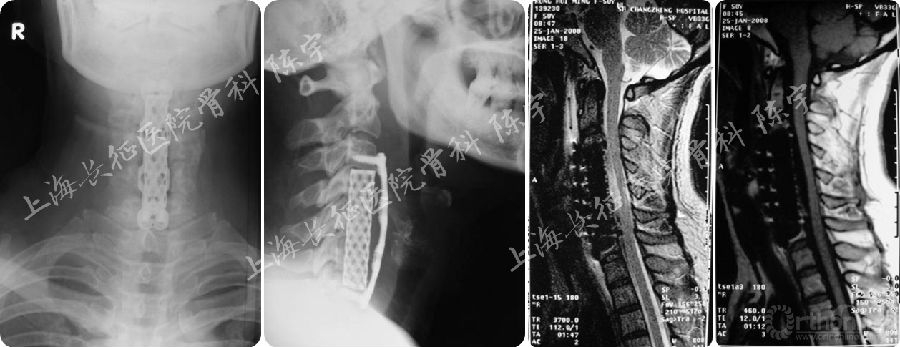

术后影像学检查(图2):

(1) X线:显示颈前路C4-6椎体次全切除减压钛网植骨融合术;

(2) MRI:显示术后脊髓减压充分,脊髓形态完全恢复;

(3) CT: 显示后纵韧带骨化物完全切除,硬膜囊骨化保留并向前漂移。